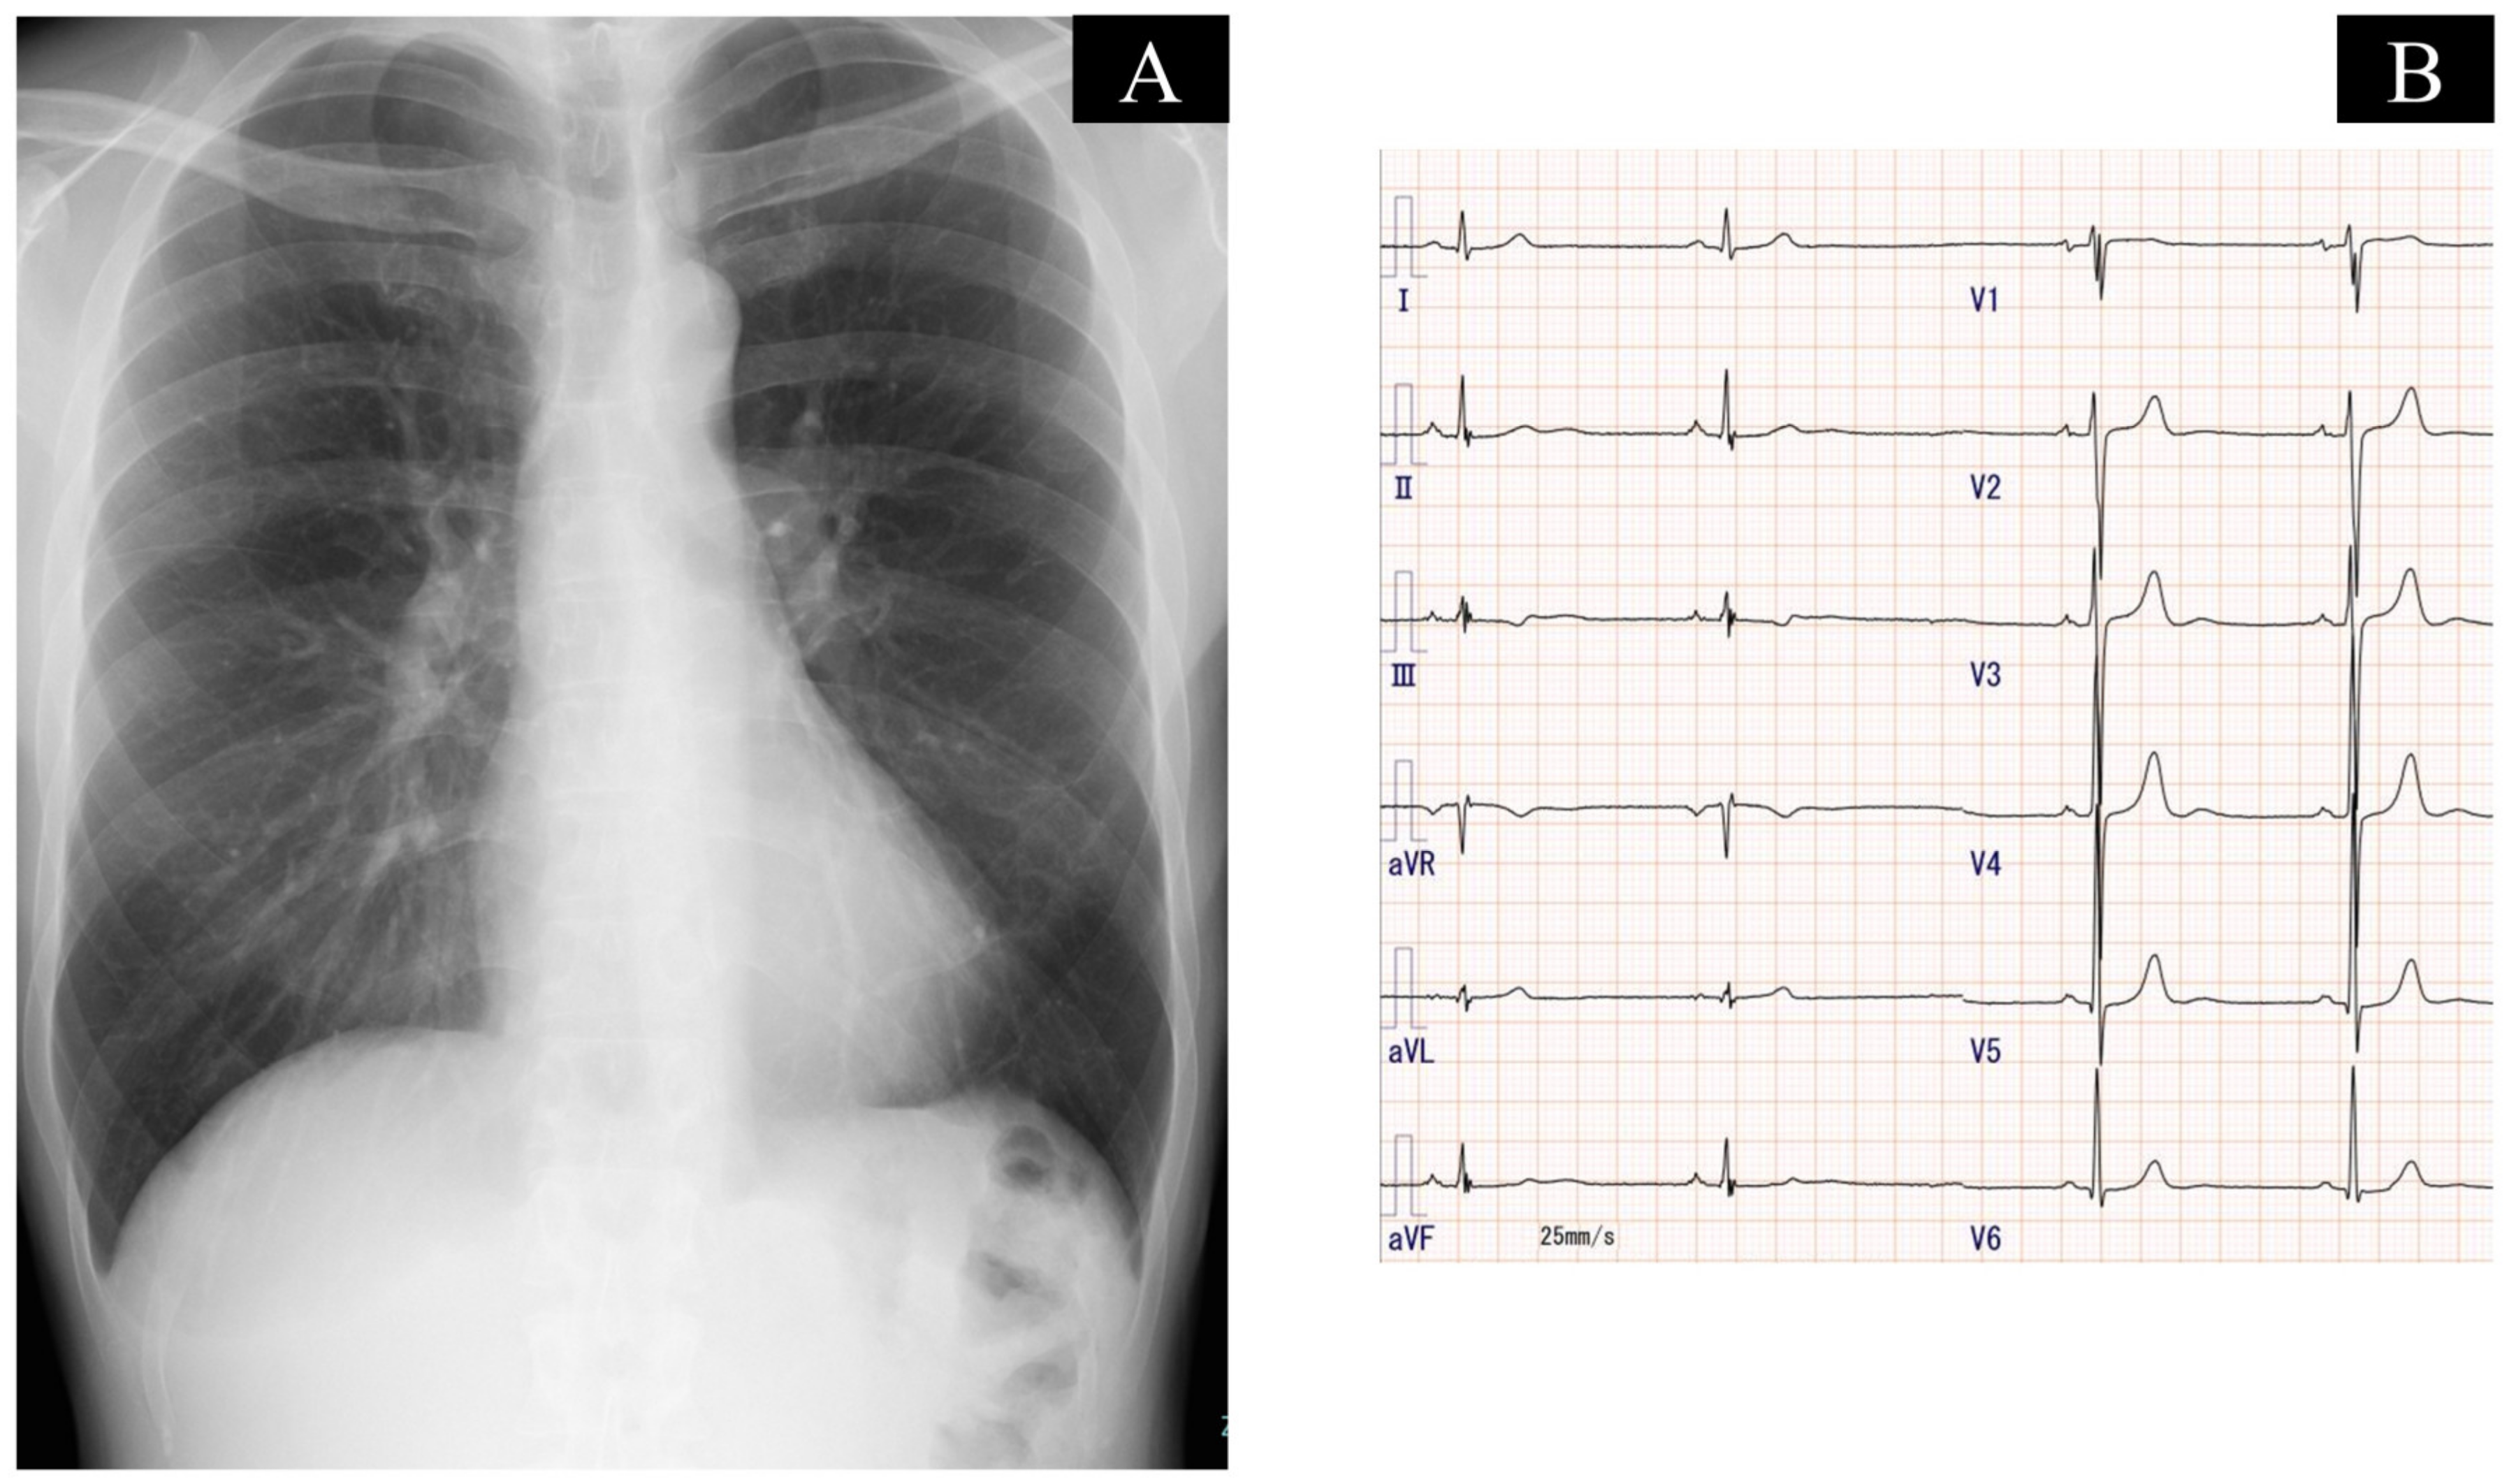

2.3. On Admission